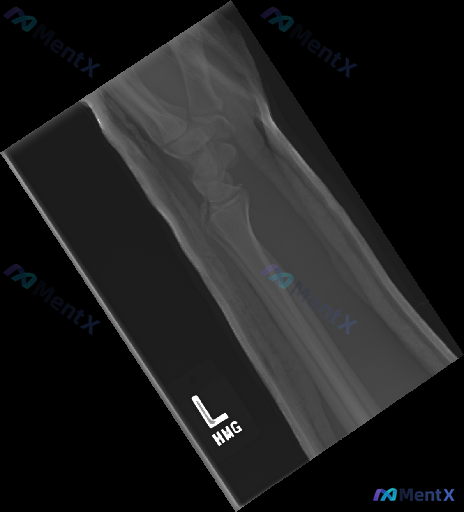

大家好,今天我们来讨论一份左侧腕部外伤后的X光片资料。先给大家看一下三个体位的影像学观察结果: 1. 放射影像-手腕处X光片-正位 (AP View) 骨骼完整性: 桡骨远端: 桡骨远端干骺端见明显骨折线,皮质连续性中断,呈现典型的背侧移位(Colles骨折特征),伴有明显的背侧成角和嵌插表现。桡骨...

整理到一份左前臂及腕部侧位X光片的影像资料,先和大家同步客观所见的线索: 1. 骨骼方面:桡骨远端背侧和掌侧皮质有连续性中断,可见骨折线涉及关节面,断端有背侧移位、背侧成角的表现,局部有粉碎或压缩改变;尺骨远端(尺骨茎突)处也可见透亮线。 2. 关节方面:桡腕关节的对应关系有改变,随桡骨移位出现背侧...

整理到一张左手腕及前臂正位X光片及配套的影像学观察内容,先把客观表现列出来,大家一起读片讨论: 影像客观表现 - 骨骼:桡骨远端可见骨质断裂线,涉及关节面,骨折端有移位和粉碎表现,骨皮质连续性中断,断端有台阶样改变;尺骨茎突也可见骨质断裂线,呈撕脱性表现;舟骨、月骨等腕骨形态大致正常;桡尺骨干皮质连...

【病例资料】 影像资料:左侧前臂侧位X光片 临床背景:成人,考虑创伤相关表现 从这张图像中可以注意到一些与正常情况不符的征象,包括骨皮质改变、关节对位、周围软组织等方面的异常。 想先听听大家的第一判断倾向——单看这张侧位片的表现,你更倾向于首先考虑哪类核心异常?